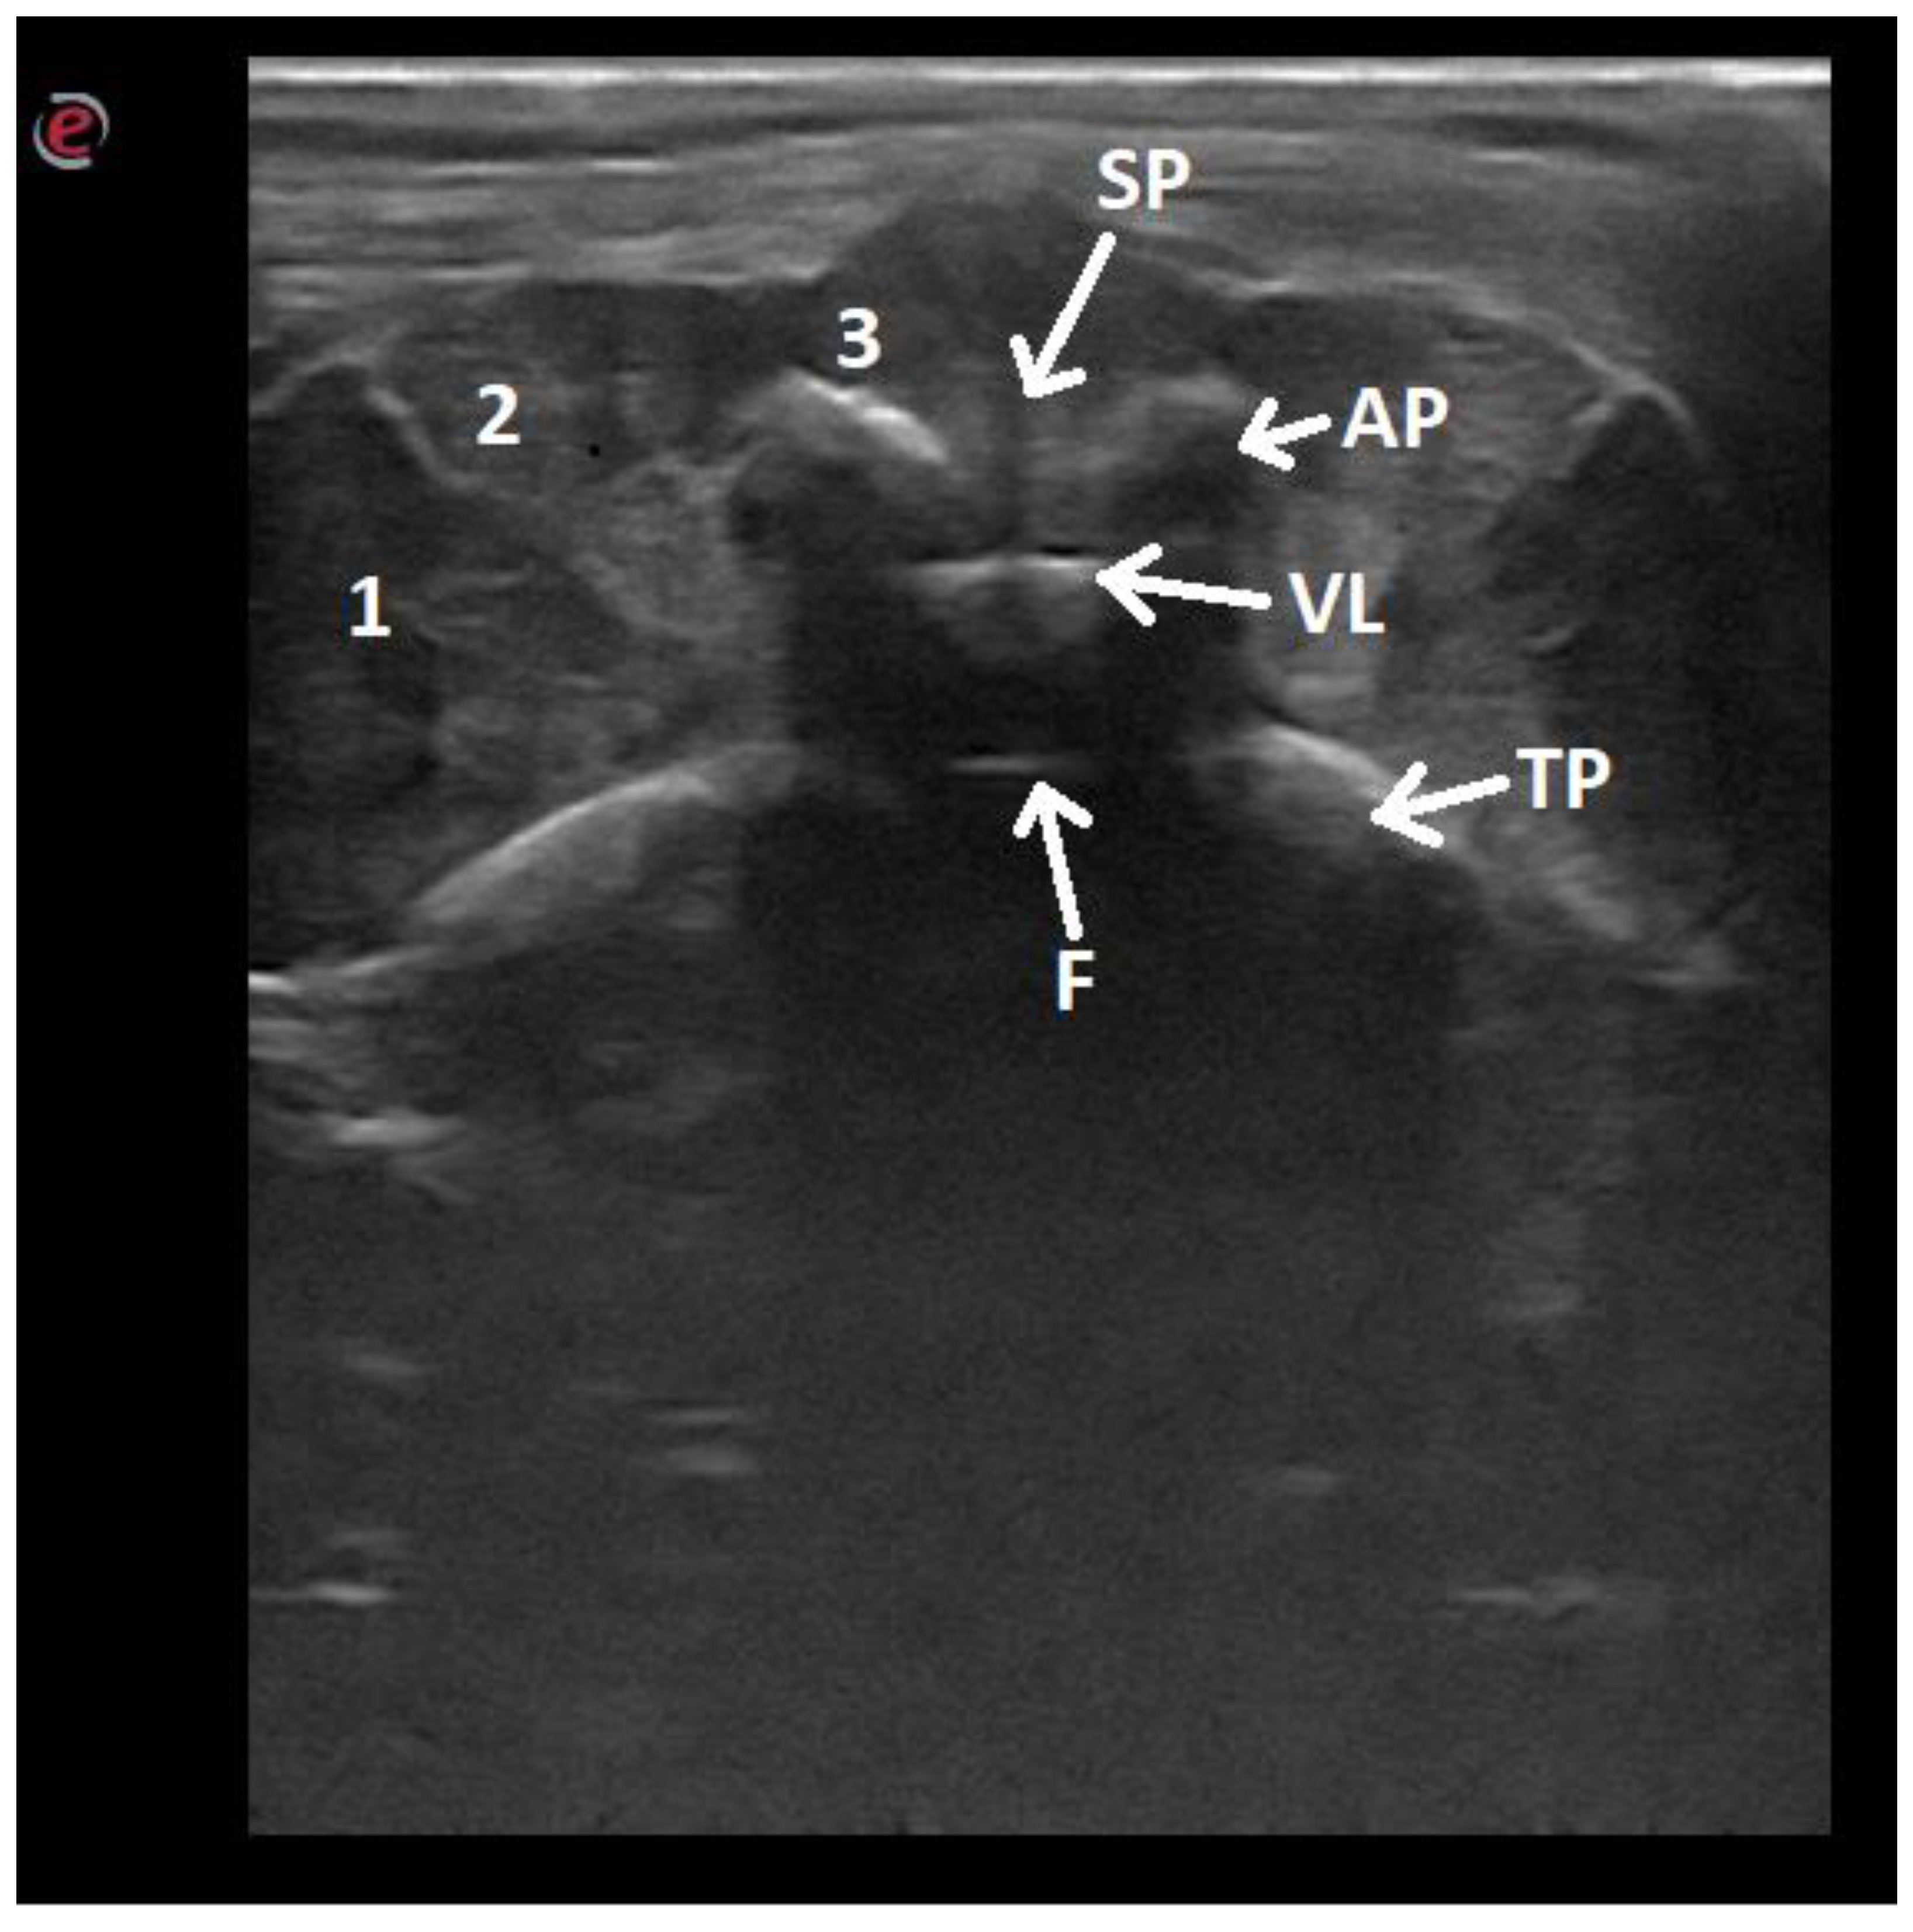

| Articular processes | 12/52.17 |

| Transverse processes | 15/65.22 |

| Vertebral body | 23/100 |

| Intervertebral discs | 23/100 |